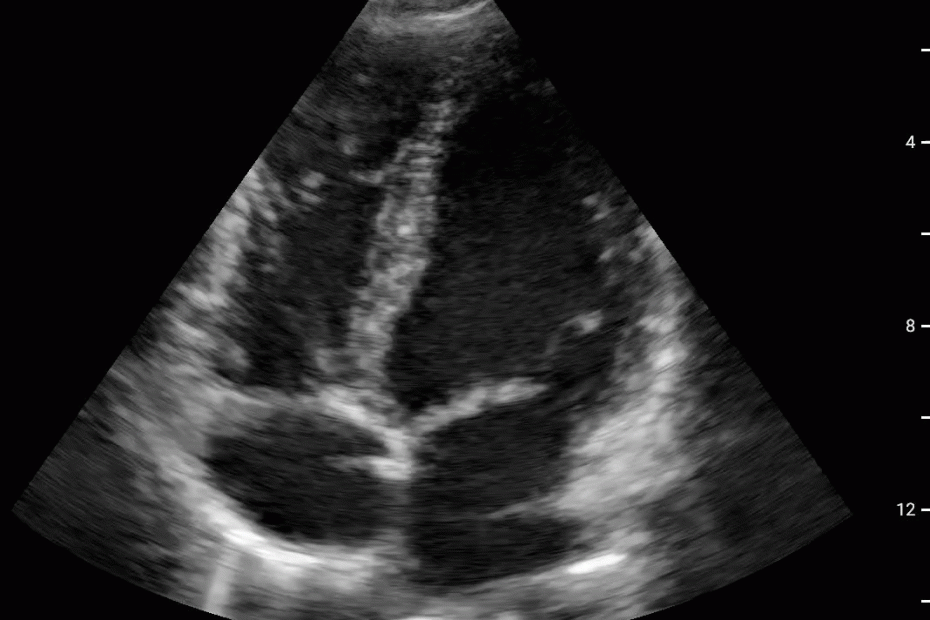

Pericardial and Pleural Effusions

Pericardial Effusion

Pacer Lead Migration

Mitral Valve Prolapse

Left Atrial Mass

Complete Heart Block

Atrial Flutter

Supine vs Left Lateral Decubitus

Normal 4 View Echo